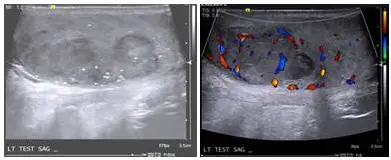

38歲男性病人,因左側睪丸腫塊就診,超音波影像如附圖,最可能為下列何者?

本題測驗陰囊超音波(Scrotal Ultrasound)在鑑別睪丸腫塊(Testicular mass)的臨床應用。重點在於判斷病灶是囊性(Cystic)或實質性(Solid)、位於睪丸內(Intratesticular)或睪丸外(Extratesticular),以及透過彩色都卜勒超音波(Color Doppler)評估血流分布,進而區分良性病變與惡性腫瘤。

- 左圖(灰階超音波,B-mode US):影像標示為「LT TEST SAG」(左側睪丸矢狀切面)。在睪丸實質內可見一個體積龐大、邊緣呈分葉狀(lobulated)、相對於正常睪丸組織呈現**低回音(Hypoechoic)**的實質性腫塊。腫塊內部回音略顯不均勻,且伴隨散在的微小高回音點(可能為微小鈣化 microcalcifications)。

- 右圖(彩色都卜勒超音波,Color Doppler US):針對同一病灶開啟彩色都卜勒模式,可見該低回音腫塊內部具有豐富的血流訊號(Hypervascularity)。 綜合影像結論:這是一個位於「睪丸內」的「實質性」、「低回音」且「血流豐富」的腫塊,在臨床超音波診斷上,此類影像特徵高度懷疑為惡性睪丸腫瘤。